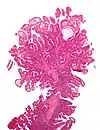

| Adénome dentelé sessile | Semblable à hyperplasique avec hyperserration, bases des cryptes dilatées/ramifiées, des cellules de mucine apparents à la base des cryptes | Oui | ![]() |

||